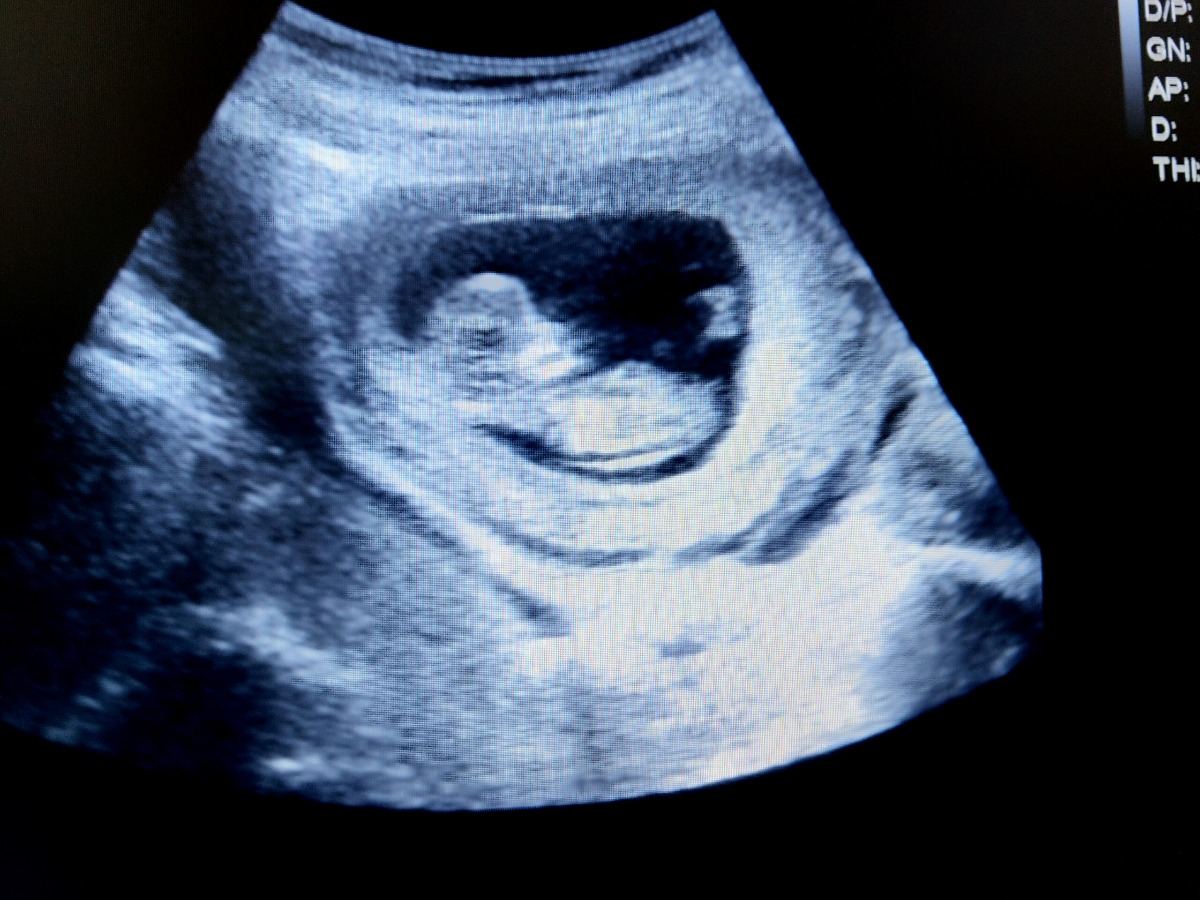

Nếu nhìn ảnh siêu âm mẹ sẽ thấy phần đầu của bé vẫn rất to. So với tuần trước, mặt của bé đã rộng hơn và 2 mắt cũng tách xa nhau hơn. Phần tai phía trên của bé đã mọc lên nhiều, có độ cong rõ, tuy nhiên vẫn chưa thể giống như một chiếc tai hoàn chỉnh.

Bộ phận sinh dục của bé vẫn đang phát triển nhưng qua ảnh siêu âm sẽ rất khó để xác định được chính xác bé là trai hay gái ở thời điểm này.